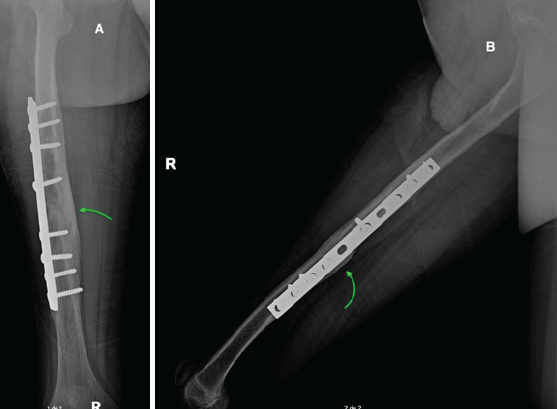

He was discharged on postoperative day 2 with close follow-up scheduled. At 3 weeks, the patient was asymptomatic, with proper wound healing and functional mobility. Radiographs confirmed maintained reduction and early consolidation (Fig. 2). At 6 months, he remained pain-free with good hip mobility and radiological evidence of Grade IV callus formation (Fig. 3).

Figure 3: X-ray 6 months follow-up. Anteroposterior (A) and lateral (B) radiographs at 6-month follow-up showing Grade IV consolidation with prominent callus formation (green arrow), osteosynthesis material without signs of fatigue or loosening, and proper alignment without rotation or angular deformities.